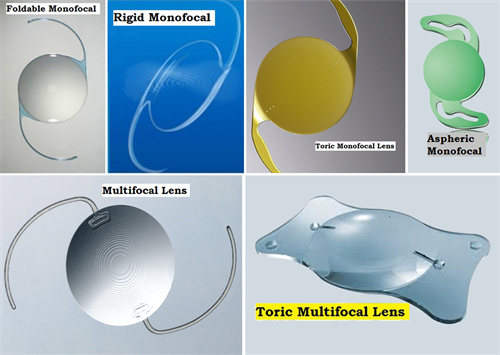

白内障手术是一种非常常见且安心的眼科手术,通常采用超声乳化技术将模糊的晶状体取出,然后植入人工晶状体以改善眼部视力。